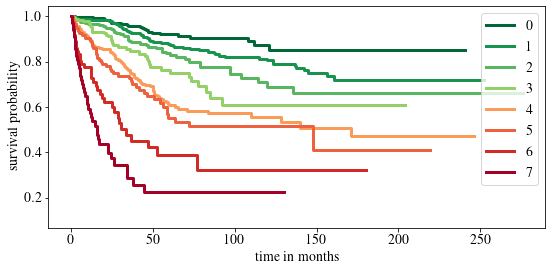

In addition, we assign individual patients to 8 risk groups, to enable a relative ranking as detailed in \appendixrefapd:risk_strat. Risk groups further allow the evaluation of Kaplan-Meier curves (Kaplan and Meier, 1958) with a log-rank test, which is common in survival analysis (Li et al., 2015). Kaplan-Meier curves are calculated for the risk groups on the training, validation and test datasets. Overall, we can show that the risk groups stratify well on all sets. The results for the test set are shown in \figurereffig:risk_stratification, where five out of seven log-rank tests pass ().

For the selection of the interval limits, multiple possible interval limits are defined and the best combination is chosen as follows. For each possible combination, the patients are assigned to the risk groups and patients within one group are combined in a single Kaplan-Meier curve (Kaplan and Meier, 1958). The resulting Kaplan-Meier curves per risk group are tested for discrimination power with a log-rank test, which is commonly used in survival analysis (Li et al., 2015). Since the proposed model allows for nonproportional hazards and therefore crossing survival curves, the log-rank test is modified with Fleming-Harrington weights according to Fleming and Harrington (2005). If the test passes, the survival curves stratify well. Multiple combinations of boundaries can give perfectly stratified curves on the training set, which is why the best suited limits are further evaluated on the validation set. The limits with the best results on the validation set are used for final evaluation on the test set. The number of risk groups is also varied in this procedure, since using too few risk groups gives good stratification but is not meaningful for patients, whereas using too many risk groups, the Kaplan-Meier curves cannot separate well any more. In our analysis, using 8 risk groups was the largest number of possible groups that led to the best possible stratification in the training set. The found interval limits are 0.06, 0.12, 0.15, 0.18, 0.3, 0.42 and 0.51. Resulting Kaplan-Meier curves on the test set are shown in \figurereffig:risk_stratification. While all groups separate well in the training set, one log-rank test fails in the validation set and two tests fail for the test set. As limit for the p-value, 0.05 is chosen.